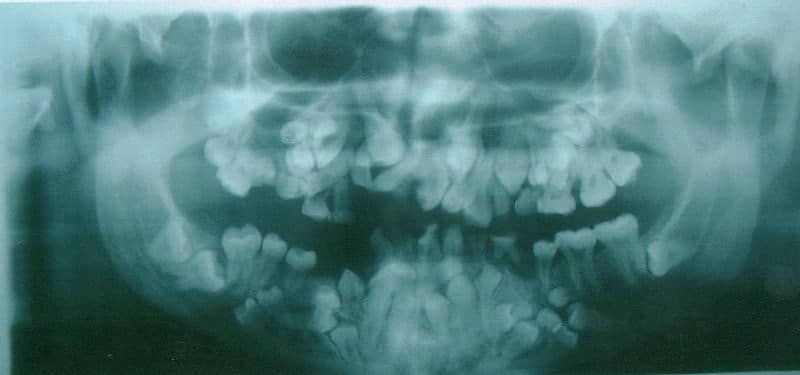

Teeth are organised into two opposing arches – maxillary (upper) and mandibular (lower). These can be divided down the midline (mid-sagittal plane) into left and right halves. Teeth are positioned in alveolar sockets, and connected to the bone by a suspensory periodontal ligament. In this article, we shall look at the development of the teeth – their precursor tissues, differentiation, and related clinical conditions. Pro Feature - 3D Model You've Discovered a Pro Feature Access our 3D Model Library Explore, cut, dissect, annotate and manipulate our 3D models to visualise anatomy in a dynamic, interactive way. Learn More Embryological Development Teeth develop and erupt at different times as a result of a complex, multi-step process, involving the patterning of inductive signals and homeobox genes. Signalling occurs between the oral epithelium and the underlying mesenchyme. Temporal and spatial control of gene expression leads to formation of different tooth types. Tooth development is recognised to occur in stages – initiation, morphogenesis, and differentiation. Initiation Tooth initiation begins at the 6th week in utero, when ectomesenchymal cells accumulate immediately below the oral epithelium. These cells are thought be derived from the neural crest cell population. The oral epithelium then proliferates down into the ectomesenchyme to form a primary epithelial band. At the 7th week in utero, the primary epithelial band differentiates into the vestibular and dental laminae: Vestibular lamina – forms the oral vestibule (the external opening to the oral cavity) Dental lamina – forms the teeth Within the dental lamina, epithelial swellings form – these are known as the dental buds, of which there are 10 in each jaw. They give rise to the enamel organs (precursor to tooth enamel), signalling the first stages of individual tooth type development. Beneath the enamel organs, ectomesenchymal tissue condenses to form the dental papilla (precursor to dentin and pulp). By Dozenist [CC-BY-SA-3.0], via Wikimedia Commons Fig 1The enamel organ and dental papilla. Morphogenesis Morphogenesis commences at the 10th week in utero, when five developing tooth germs appear in each quadrant, which give rise to the primary dentition. By the 16th week in utero, the tooth germs of the permanent incisors and the 1st permanent molars begin to form. The 2nd and 3rd permanent molar tooth germs appear long after birth. Differentiation By the 18th week in utero, differentiation of tooth germs has occurred and dental hard tissue has formed. Alveolar bone forms around the developing dental follicle. Later Development The process of tooth development continues for a period in excess of 10 years, whereas the process of tooth eruption continues for almost 20 years. Developmental disturbances that occur at any time during the period of tooth formation, may result in anomalies of tooth number, size, shape or structure. Clinical Relevance Hypodontia and Hyperdontia Hypodontia is a condition in which fewer teeth form than is expected. Teeth that most commonly fail to form are the 3rd molars, the second premolars, and the lateral incisors. Ectodermal dysplasia is a condition in which multiple teeth are developmentally absent. Hyperdontia is where supernumerary, or supplemental, teeth are formed, in addition to the normal expected series. These teeth often have an unusual morphology. They may erupt, or may remain unerupted. They may prevent eruption of teeth in the normal series. Cleidocranial dysplasia is a condition in which multiple supernumerary teeth form. By Garg RK, Agrawal P [CC BY 2.0], via Wikimedia Commons Fig 2X-ray of cleidocranial dysplasia, demonstrating multiple unerupted supernumerary teeth. Do you think you’re ready? Take the quiz below Pro Feature - Quiz Development of the Teeth Question 1 of 1 Submitting... Skip Next Rate question: You scored 0% Skipped: 0/1 1800 More Questions Available Upgrade to TeachMeAnatomy Pro Challenge yourself with over 1800 multiple-choice questions to reinforce learning Learn More Rate This Article